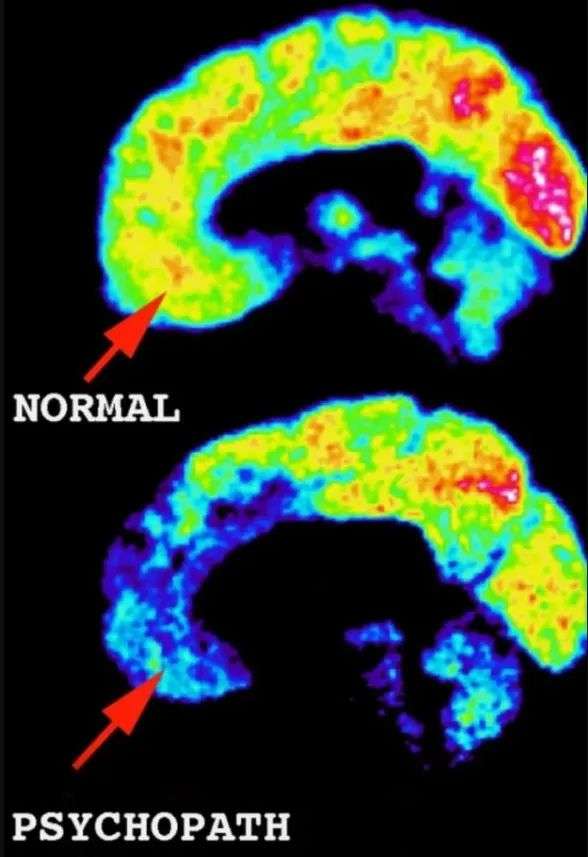

在多年的脑部扫描分析中,他注意到,冷酷顽固的凶手在大脑的额叶和颞叶——与同理心和自我控制相关的区域——的活动低得惊人。因为没有自制力,他们就成了疯狂的杀手。

与正常成年人相比,精神病患者的 PET 扫描显示社交和情感中心的大脑活动减少。

与健康的大脑相比,杀手的大脑在眶皮层和杏仁核周围的活动要少得多——这些区域可以防止冲动行为并控制社会行为、抑制、道德和伦理。

而他的脑部扫描,确实明明白白显示着同样的杀手模式。他的大脑在眼睛后面那个关键的眶皮层区域有黑色的低活动斑块。

“大脑该区域活动低下的人是随心所欲的人或反社会者,”他说。